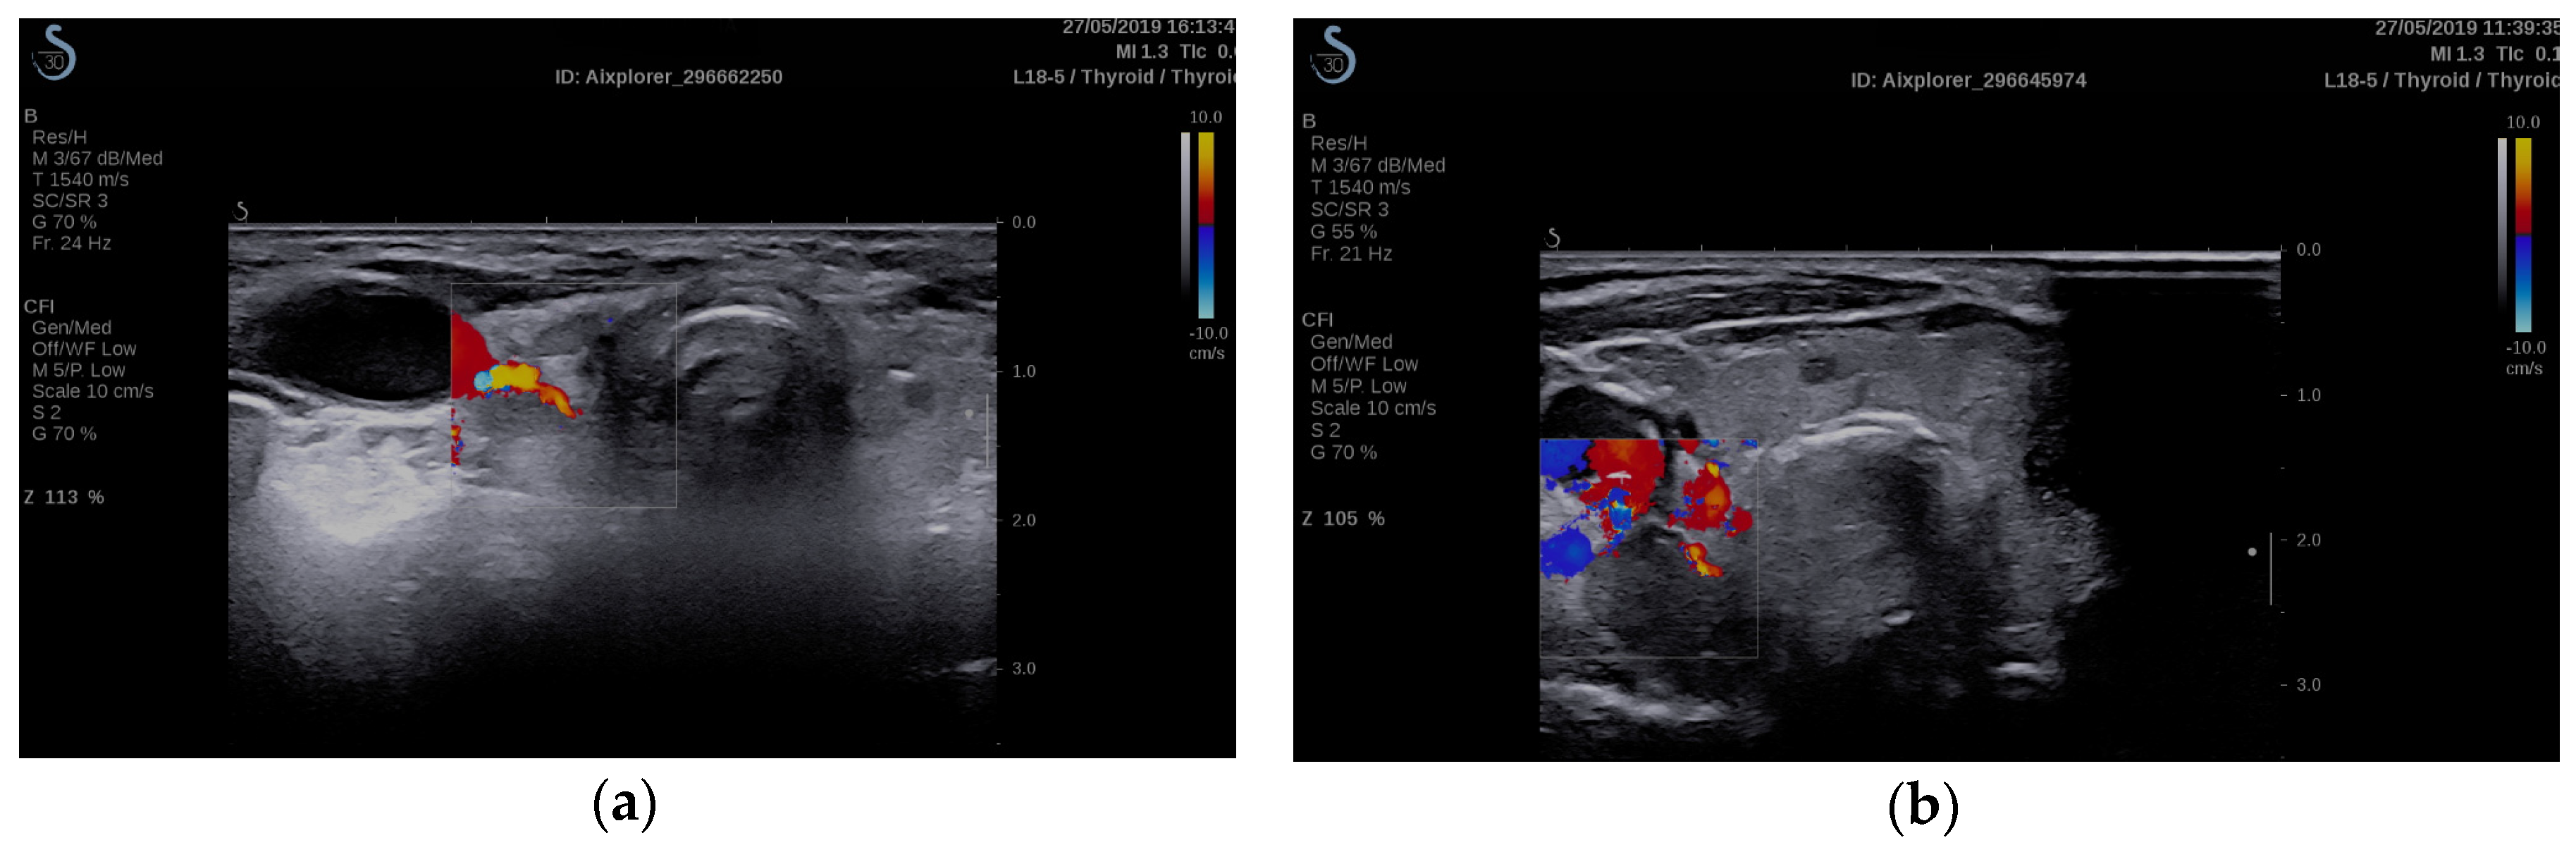

- Cotoi, L.; Borcan, F.; Sporea, I.; Amzar, D.; Schiller, O.; Schiller, A.; Dehelean, C.A.; Pop, G.H.; Stoian, D. Shear wave elastography in diagnosing secondary hyperparathyroidism. Diagnostics 2019, 9, 1–16. [Google Scholar] [CrossRef]

- Cotoi, L.; Amzar, D.; Sporea, I.; Borlea, A.; Navolan, D.; Varcus, F.; Stoian, D. Shear Wave Elastography versus Strain Elastography in Diagnosing Parathyroid Adenomas. Int. J. Endocrinol. 2020, 2020, 1–11. [Google Scholar] [CrossRef]